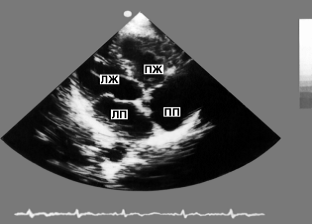

Рис. 1. Схема основных доступов для ультразвукового исследования сердца в сечении длинной оси (а), короткой оси (б) и с обозрением четырех камер сердца (в): 1 - парастернальная позиция датчика, место локации в III-IV межреберьях слева от грудины; 2 - верхушечная позиция, место локации в IV-V межреберьях по левой среднеключичной линии; 3 - супрастернальная позиция, локация со стороны яремной ямки; 4 - субкостальная позиция, локация со стороны эпигастральной области. Исследуемые структуры сердца на этом и других рисунках к статье имеют обозначения: АО - аорта, ЛЖ - полость левого желудочка, ЛП - полость левого предсердия, ПЖ - полость правого желудочка, ПП - полость правого предсердия

Рис. 8. Двухмерная эхокардиограмма из верхушечного доступа: видны полости всех четырех камер сердца (темные поля) в поперечном сечении, разделенные перегородками и створками атриовентрикулярных клапанов (светлые структуры)